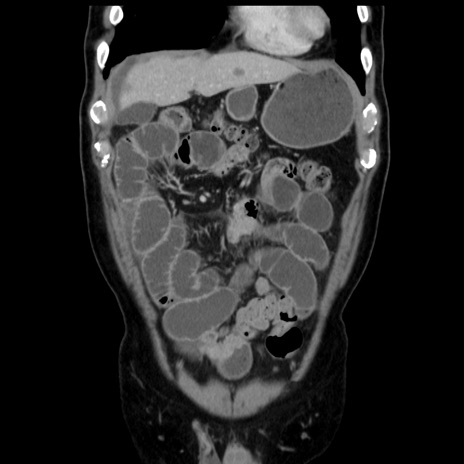

症例16(冠状断像)

【症例】 70歳代男性

【主訴】 腹痛、嘔吐

【現病歴】 約1ヶ月前より間欠的に腹痛と嘔吐あり、当院消化器内科を受診したところCTで多発する肝臓のLDAを指摘され、精査中であった。以降は消化器症状は安定していたが、2日前より嘔気と腹痛があり、同日より排便・排ガスが消失した。改善認めず、 本日、救急外来を受診した。

【既往歴】 大腸ポリープ切除後。

【身体所見】意識清明・会話良好、BT 36.3℃、BP 127/80mmHg、 P 80bpm、腹部:膨満あり、平坦・軟、上腹部正中および下腹部正中に圧痛あり、反跳痛なし、筋性防御なし。

【データ】WBC 7200、CRP 0.77